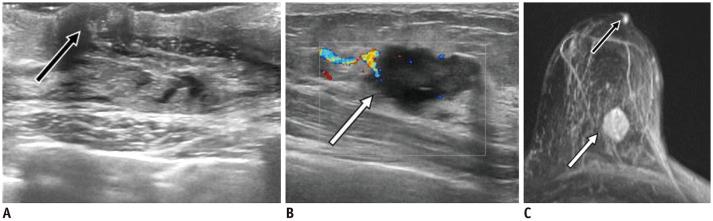

Ultrasound (US) is an attractive diagnostic approach to identify both common and uncommon nipple pathologies, such as duct ectasia, nipple abscess, nipple leiomyoma, nipple adenoma, fibroepithelial polyp, ductal carcinoma (restricted to nipple), invasive carcinoma, and Paget's disease. US is the reliable first-line imaging technique to assess nipple pathologies. It is useful to identify and characterize nipple lesions. Additionally, we have presented the mammography and MRI outcomes correlated with histopathologic features for the relevant cases.